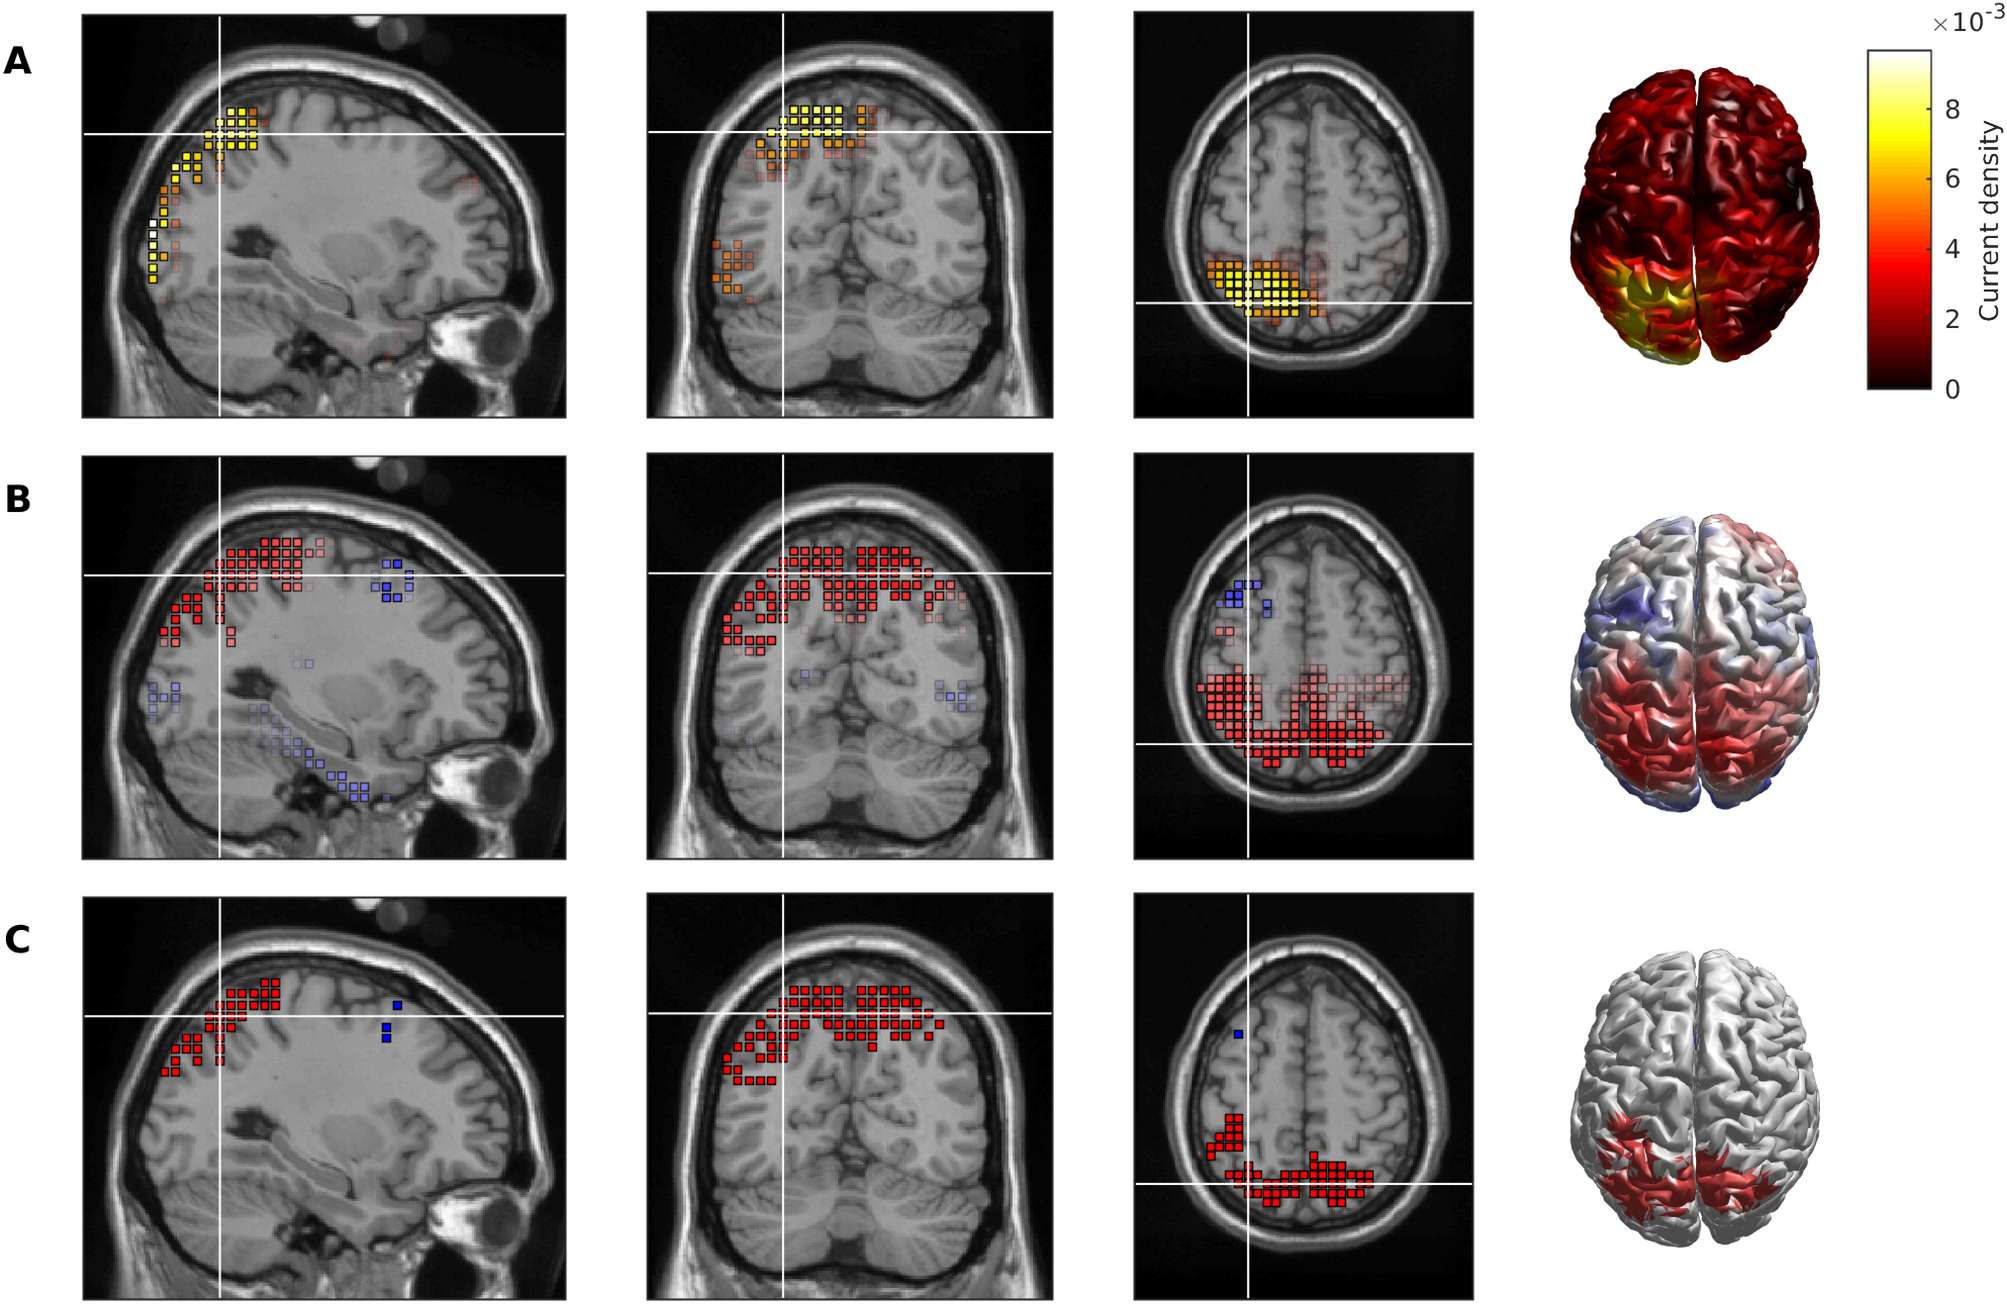

Figure 2

Cortical source generators underpinning alterations to microstate class D in AD. (A) Absolute value of the eLORETA solution to the instantaneous topography given by taking the difference between the global class D maps for HOA and AD. (B) t-statistic for voxel-wise comparisons of the subject-wise class D maps for HOA versus AD. Red indicates absolute value of current density is larger for HOA than AD, whilst blue is AD > HOA. (C) Voxels with t-values such that P < .05. Red voxels indicate HOA > AD, and blue voxels are AD > HOA.